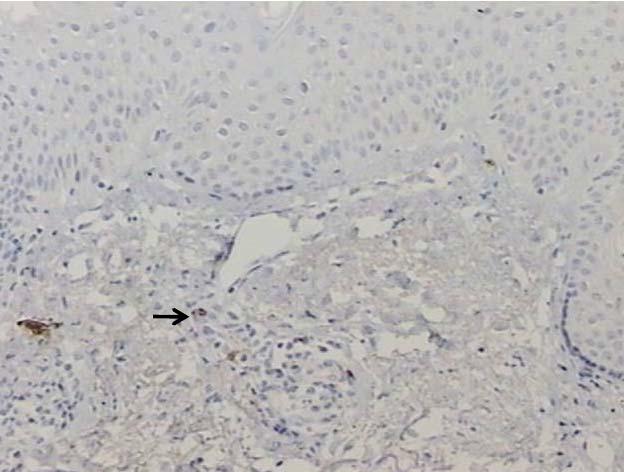

CD20

Ausente 1 12,5 1 11,1 0 0,0

0,0339

Raras 7 87,5 7 77,8 1 25,0

Leve 0 0,0 1 11,1 3 75,0

Total 8 100,0 9 100,0 4 100,0